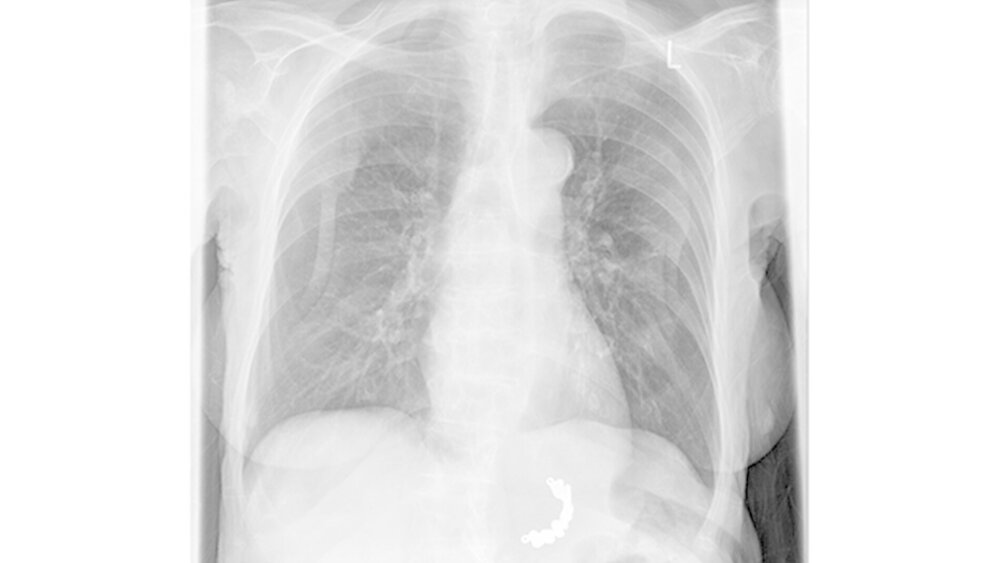

Die anschließend durchgeführte Gastroskopie zeigte eine „Nekrose-Zone im Bereich des oberen Ösophagussphinkters“ sowie „eine große Perforation des oberen Ösophagus“. Nach der Entfernung der Prothese mittels Schlinge wurde die Patientin zur palliativen Weiterbehandlung auf die Station verlegt. Die Patientin verstarb am darauffolgenden Tag.